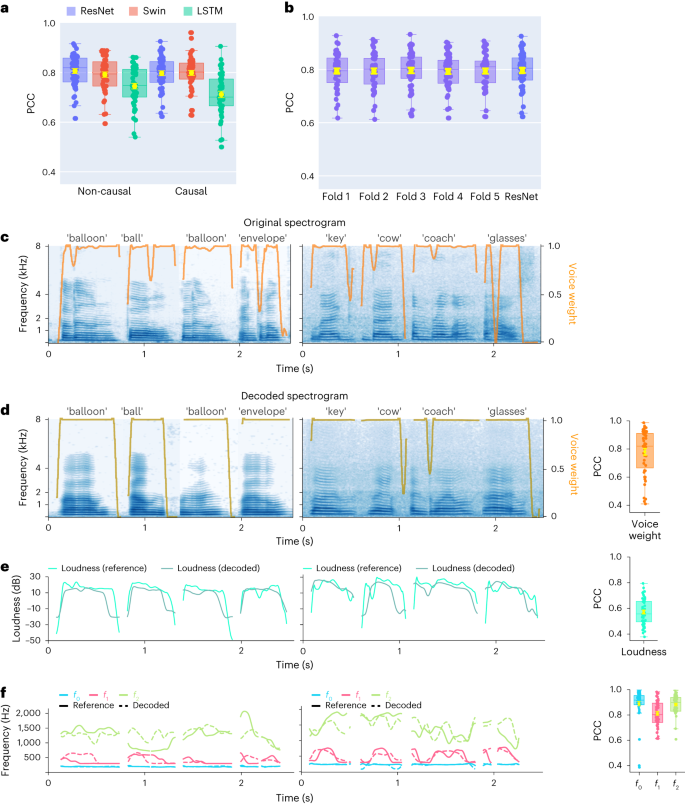

2 Model Architecture

Following [ 9 ] , the proposed system consists of three components: a speaker encoder , which computes a fixed-dimensional embedding vector from a few seconds of reference speech of a target speaker; a synthesizer , which predicts a mel spetrogram from an input text and an embedding vector; a neural vocoder , which infers time-domain waveforms from the mel spectrograms generated by the synthesizer. At inference time, the speaker encoder takes as input a short reference utterance of the target speaker and generates, according to its internal learned speaker characteristics space, an embedding vector. The synthesizer takes as input a phoneme (or grapheme) sequence and generates a mel spectrogram, conditioned by the speaker encoder embedding vector. Finally the vocoder takes the output of the synthesizer and generates the speech waveform. This is illustrated in Figure 1 .

2.3 Synthesizer and Vocoder

The synthesizer component of the system is a sequence-to-sequence model with attention [ 1 , 3 ] which is trained on pairs of text derived token sequences and audio derived mel spectrogram sequences. Furthermore, the network is trained in a transfer learning configuration (see Paragraph 2.4 ), using an independently-trained speaker encoder to extract embedding vectors useful to condition the outcomes of this component. In view of reproducibility, the adopted vocoder component of the system is a Pytorch github implementation 1 1 1 https://github.com/fatchord/WaveRNN of the neural vocoder WaveRNN [ 15 ] . This model is not directly conditioned on the output of the speaker encoder but just on the input mel spectrogram. The multi-speaker vocoder is simply trained by using data from many speakers (see Section 3 ).

2.4 Transfer Learning Modality

The conditioning of the synthesizer via speaker encoder is the fundamental part that makes the system multi-speaker: the embedding vectors computed by the speaker encoder allow the conditioning of the mel spectrograms generated by the synthesizer so that they can incorporate the new speaker voice. In [ 9 ] , the embedding vectors are speaker embeddings obtained by Equation 2 . We used the utterance embeddings computed by Equation 1 . In fact, at inference time only one utterance of the target speaker is fed to the speaker encoder which therefore produces a single utterance-level d-vector. Thus, in this case, it is not possible to create an embedding at the speaker level since the average operation cannot be applied. This implies that only utterance embeddings can be used during the inference phase. In addition, an average mechanism could cause some loss in terms of accuracy. This is due to larger variations in pitch and voice quality often occurring in utterances of the same speaker while utterances have lower intra-variation. Following [ 9 ] , the embedding vectors computed by the speaker encoder are concatenated only with the synthesizer encoder output in order to condition the synthesis. However, we experimented with a new concatenation technique: first we passed the embedding through a single linear layer and then we applied the concatenation between the output of this layer and the synthesizer encoder one. The goal was to exploit the weights of the linear layer to make the embedding vector more meaningful, since the layer was trained together with the synthesizer. We noticed that this method achieved good convergence of training and was about 75% times faster than the former vector concatenation.